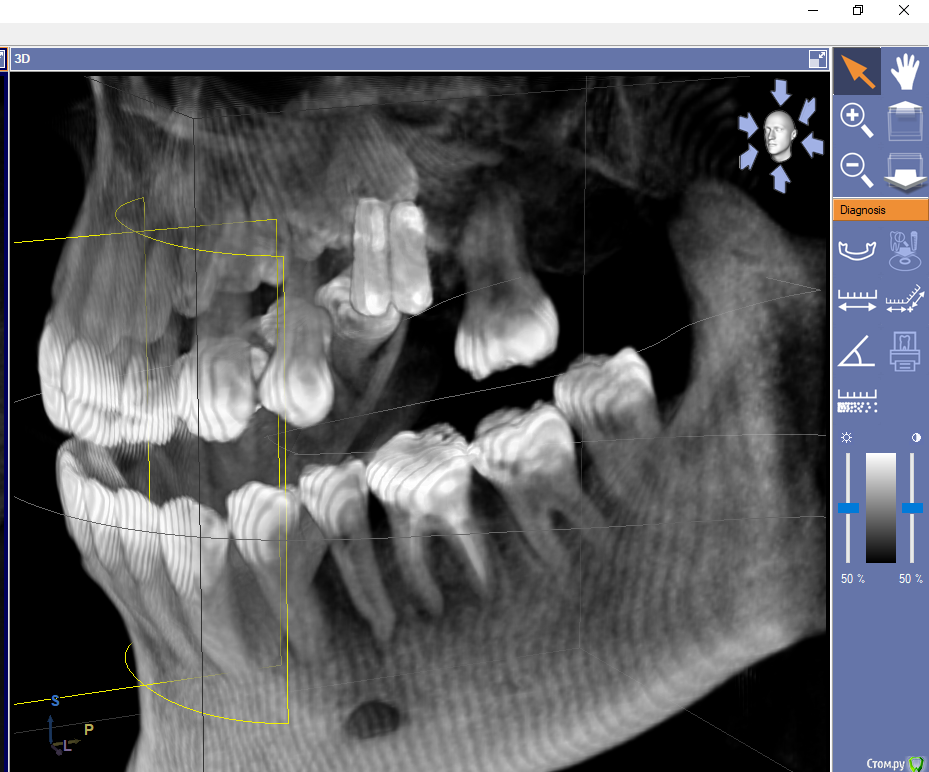

layraldo Опубликовано 4 декабря, 2019 Поделиться Опубликовано 4 декабря, 2019 Здравствуйте! Подскажите, пожалуйста, насчет ситуации. Весной этого года были установлены два импланта (вроде Nobel Biocare), перед этим был сделан синуслифтинг. Недавно пошла удалять зуб и там хирург, посмотрев на снимок челюсти, сказала, что импланты установлены неверно, очень близко друг к другу, и что они выпадут в течение года. Есть ли шанс, что они прослужат дольше и если прогноз неблагоприятный, то что делать? Врач-ортопед из клиники, где были установлены импланты ничего по поводу снимка не сказал. Ссылка на комментарий

dok1 Опубликовано 5 декабря, 2019 Поделиться Опубликовано 5 декабря, 2019 Если реалии соответствуют снимку, то близко Ссылка на комментарий

Pavel-Pskov Опубликовано 6 декабря, 2019 Поделиться Опубликовано 6 декабря, 2019 Кмк при такой ситуации даже фдм сложно будет установить. 1 Ссылка на комментарий

dok1 Опубликовано 7 декабря, 2019 Поделиться Опубликовано 7 декабря, 2019 Между имплантами нет полноценных кровеносных сосудов, соответственно нет питания и полноценной кости. Ссылка на комментарий